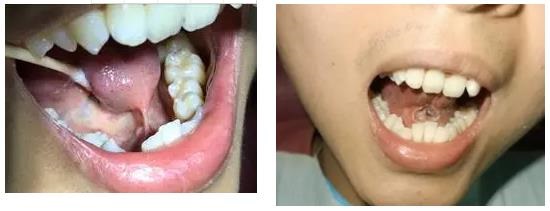

02.血管瘤和脉管畸形的治疗

利用激光能被血液中的血红蛋白选择性吸收从而凝固、变性来达到治疗目的,取代了传统的手术切除及硬化剂瘤内注射,从而降低了传统治疗方式导致的不必要的并发症。